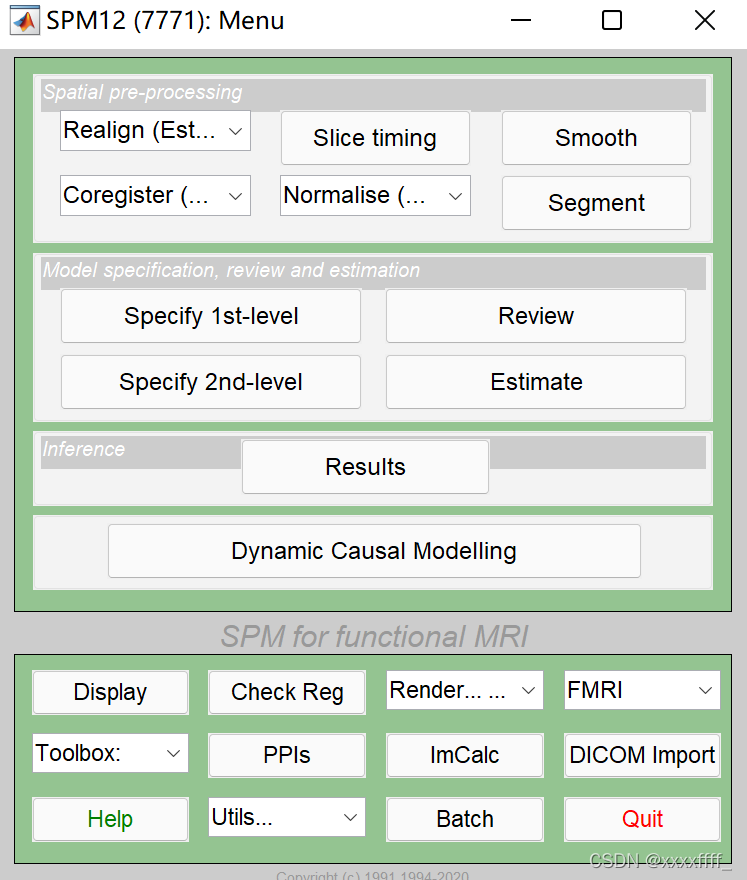

首先就是需要我们自己手动调整一下结构像,打开SPM,spm首页有PET&VBM,还有一个fMRI,亲测选哪个都可以。总之选了之后就是下面这个页面,然后点Display。